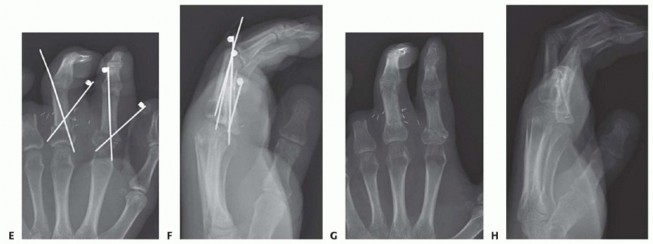

TECH FIG 3 • A-D. Parallel longitudinal K-wires allow for easy and rapid fixation with low complication rates.(continued)

TECH FIG 3 •(continued)E-H. In more proximal amputations, longitudinal K-wires may not be possible. Crossed K-wires can be used successfully in these injuries.